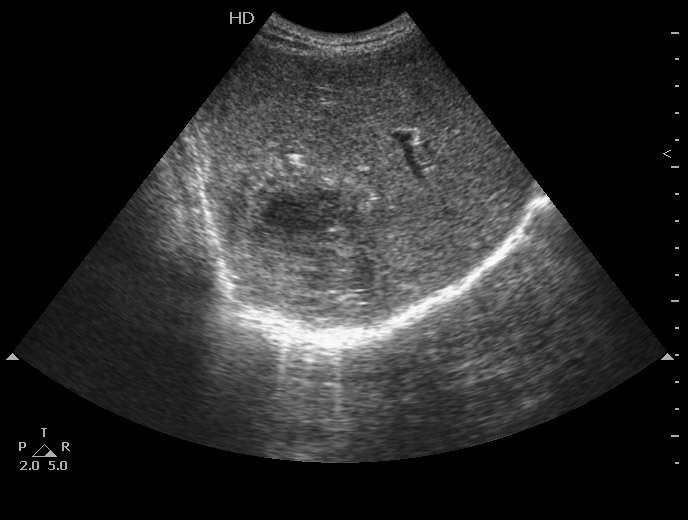

06-12-05-105726_KAZACHENKO-.jpg

06-12-05-105726_KAZACHENKO-.jpg (49.5 КБ) 1487 просмотров

Типичная картина ##1-4:

Гипоэхогенное неоднородное округлое образование, окруженное эхогенным "демаркационным валом"

измененной паренхимы печени.